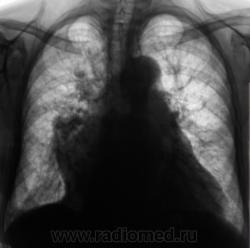

При расшифровке цифровых флюорограмм пациент "взят на контроль". Произведено стандартное исследование.

На рентгенограммах (в отличии от томо) на верхушке ничего не заметил. А так, похоже на митр. недостаточность.

Много, чего, всякого-разного мы не узреваем без "тёти Томмы". До сих пор, эта "добрая тетя", не оценена по - настоящему, а жаль...